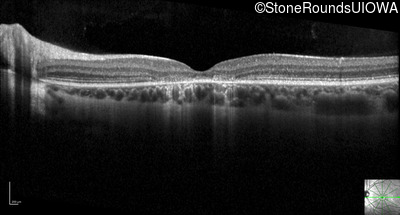

Optical Coherence Tomography - Left - 20/50 +2

Exemplar / OCT Stack